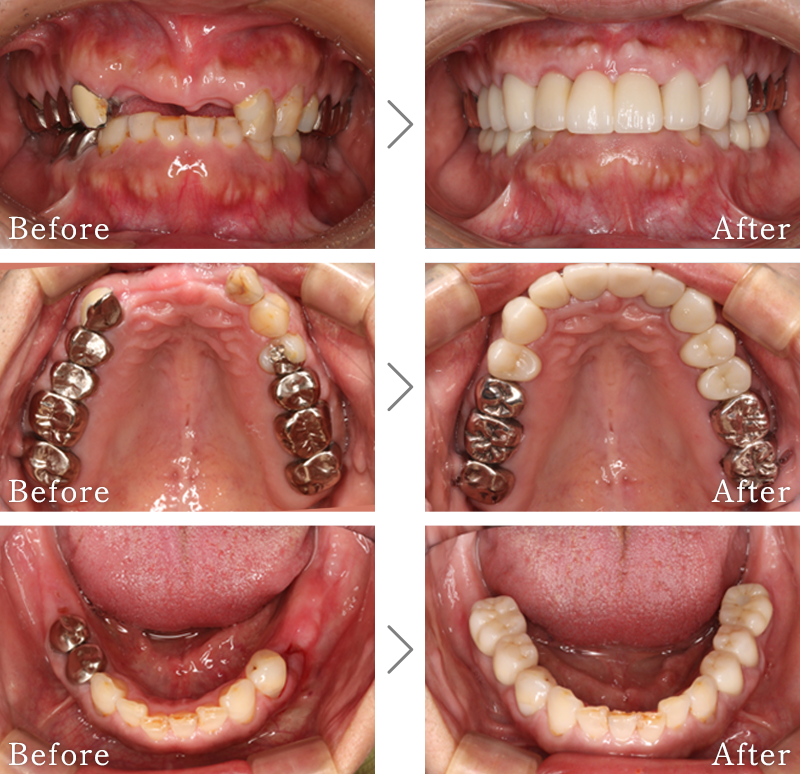

CASE6

主訴 入れ歯が合わず、痛くて噛めない。食事ができない。

治療法 入れ歯を新しく作成し、噛み合わせなどの確認をしたのち、左右2本ずつインプラントを使用して噛める状態に回復させています。

治療期間 5ヶ月

費用 CT:16,500円(税込)

+ 静脈内鎮静法:66,000円(税込)

+ インプラント治療:2,321,000円(税込)

合計:2,403,500円(税込)